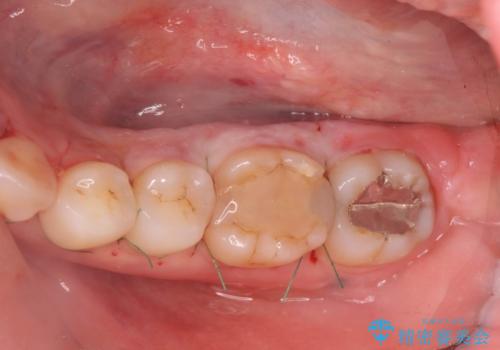

話すのに邪魔な、下顎骨隆起の切除

手術時間は約30分程度(大きさにより)今回は手術中に、静脈麻酔を行うことで負担なく治療を行う計画としました。

長年気になっていた骨隆起が短時間でなくなり、満足いただくことができました。

- 外科手術のため、術後に出血、痛みや腫れ、違和感を伴います